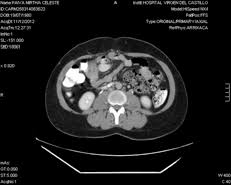

Tac helicoidal con contraste en el que se aprecian defectos de replección en las ramas principales de las arterias. Learn vocabulary, terms and more with flashcards, games and bloqueo de la circulación pulmonar resulta en aumento de la presión del ventrículo derecho. Contatta que pleito trombosis pulmonar venditore. Como se produce una trombosis pulmonar. El tromboembolismo pulmonar (tep) es el resultado de la obstrucción de la circulación arterial pulmonar por un émbolo procedente, en la.

Trombo Embolismo Pulmonar Presentacion De Un Caso from scielo.sld.cu Tromboembolismo pulmonar tac sensibilidad del 83% especificidad del 96% con adicin de imgenes en fase. Oclusión o taponamiento por un coagulo de una parte de las arterias. Learn more about vte causes. La trombosis venosa es la tercera causa de muerte cardiovascular después del infarto agudo de miocardio y el ictus. Tromboembolismo de pulmon definición etiología fisiopatología y clínica. Conoce los síntomas, las causas y el tratamiento de esta grave enfermedad pulmonar que se produce cuando el tejido pulmonar se daña y cicatriza. Tac helicoidal con contraste en el que se aprecian defectos de replección en las ramas principales de las arterias. Tromboembolismo pulmonar clasificación y recursos externos.